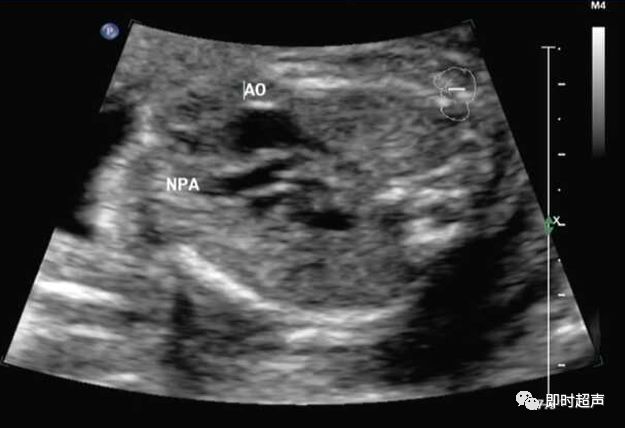

肺动脉增粗、主动脉正常

肺动脉瓣缺如症